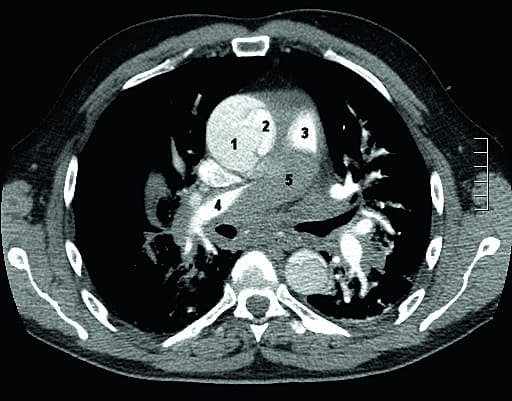

En 55-årig mand, der var tidligere rask fraset velbehandlet hypertension, blev akut indlagt på grund af vejrtrækningsbesvær og smerter i brystet, der var opstået i forbindelse med coitus. Han var kortvarigt synkoperet. Ved ankomsten var han vågen, klar og orienteret. Smerterne i brystet var aftaget, men han var udtalt dyspnøisk. Han saturerede 88-92% på 15 liter ilt på maske med reservoir. Det systoliske blodtryk lå stabilt omkring 100 mmHg. Et ekg viste sinustakykardi på 100 uden ST-forandringer. Hjerte- og lungestetoskopi viste normale forhold. Abdomen var blødt og uømt. Arterieblodgasananlyse viste lavt ilttryk og lavt partialtryk af kuldioxid, laktatniveauet var normalt, hæmoglobinniveauet var 6,5 mmol/l, og D-dimerniveauet var over 20 mg/l. På baggrund af ovenstående havde man mistanke om lungeemboli, og patienten blev kørt til akut CT af thorax. Denne viste en Stanford type A-aortadissektion med involvering af både aorta ascendens og aorta descendens. Der var tillige et stort mediastinalt hæmatom og igangværende blødning, som obstruerede de centrale lungearterier. Der var ingen lungeembolier. Patienten blev opereret på Thoraxkirurgisk Afdeling på Rigshospitalet. Peroperativt var der en større blødning. Han blev udskrevet efter 36 dage i sin habitualtilstand fraset lettere kognitive deficit.

A very rare and often fatal complication to acute Stanford type A dissection is a mediastinal haematoma with pulmonary artery obstruction. Clinically it mimics pulmonary embolism. A 55-year-old man was admitted to hospital with chest pain and severe respiratory distress. There was no sign of cardiac involvement. Pulmonary embolism was suspected and an acute computed tomography (CT) was performed. The CT showed a Stanford type A dissection and an actively bleeding mediastinal haematoma with compression of the pulmonary arteries. Emergency surgery was successfully performed and the patient survived.